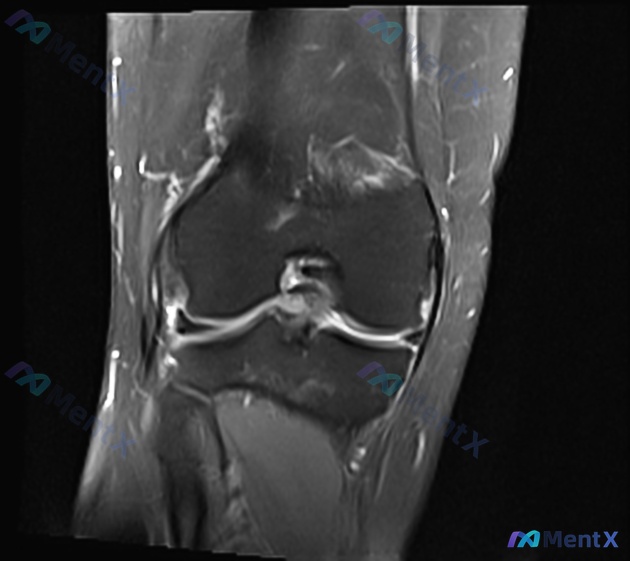

看到一个挺有警示意义的病例,整理了一下思路和大家分享。 病例基本情况 患者是一名 30岁的网球运动员,因膝关节损伤就诊,目前正在评估受影响结构的非手术治疗方案。核心问题是:哪一项临床发现与非手术治疗后关节炎变化的未来发展相关性最强? 影像与关键发现(基于提供的MRI) 这是一个矢状位的序列,从信号特...

病例背景 最近整理到一个病例资料,涉及一名 17 岁的男性高中足球运动员。 主诉与现病史 患者在两天前的比赛中受伤,随后出现右膝疼痛。就诊于儿科医生处,X 光片未见异常。 辅助检查 儿科医生建议进行膝关节 MRI 检查。影像包含冠状位和矢状位图像。 - 冠状位:脂肪抑制序列。股骨髁及胫骨平台骨皮质连...